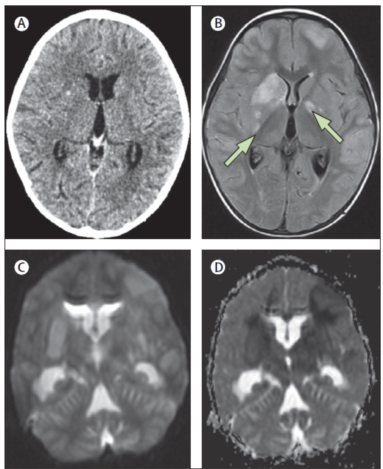

3岁,(A) Normal brain CT scan of a 3-year-old child with stage 3 tuberculous meningitis. (B) A T2-weighted, fl uid–attenuated, inverse-recovery MRI image taken 5 days later showed several infarcts (arrows) in the basal ganglia. MRIs with

diffusion-weighted imaging (C) and apparent diff usion coeffi cient (D) show restriction of diffusion and bilateral cytotoxic oedema in the basal ganglia.